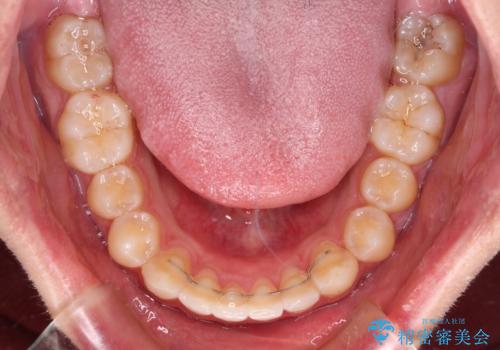

前歯のデコボコと突出感 インビザラインにて矯正治療

インビザラインによる上下歯列の側方拡大と後方移動、IPR(歯と歯の間を削る)にるスペースの獲得により歯列を整えることとしました。

左上の小臼歯は捻転が強く、あえて180逆向きの状態で終了させる治療計画としました。

ご自宅と職場がともに遠方であったため、治療期間は長くなりましたが、患者様も我々も期待して以上に口元の突出感を改善することができました。